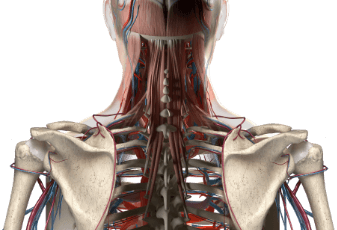

ניתוח עמוד שדרה צווארי

ניתוח עמוד שדרה צווארי - כל המידע הרפואי המעודכן בעמוד השדרה שלנו 33 חוליות. שבע העליונות, אלה המכונות C1 עד C7, נחשבות החוליות של עמוד השדרה הצווארי. בשל העובדה שהוא נתון תחת עומסים קטנים יחסית, האזור הצווארי של עמוד השדרה הוא פחות